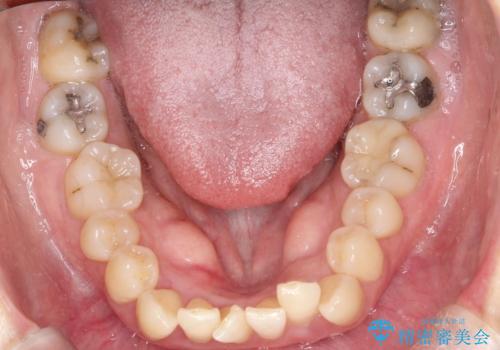

前歯が前に出ていることや歯並びの凸凹が気になるという主訴でした。十分なスペースを確保するため上下左右の第一小臼歯(4番)を抜歯し、そこに前歯を移動させて整列を行いました。矯正装置には目立ちにくい透明なブラケットを選択し、見た目のストレスを軽減。矯正期間中は定期的な通院でワイヤーを微調整し、無理なく確実に歯を動かしました。治療後は前歯が自然な位置に下がり、口元の突出感が解消されるとともに、美しく整った口元に仕上がり、患者様にも大変喜んでいただけました。